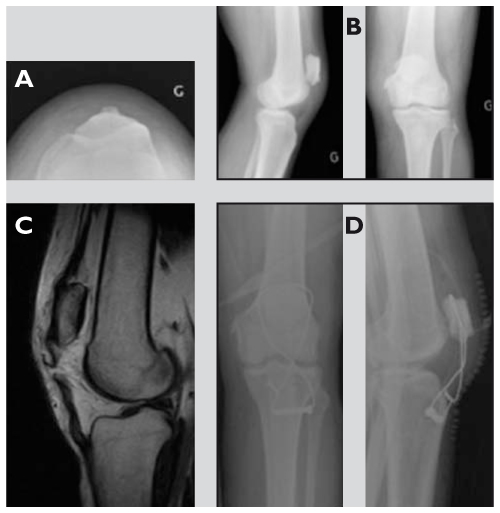

Fracture Avulsion De La Tuberosite Tibiale Anterieure Chez Un Enfant

Dr Cyril Mayer Fracture De La Rotule

Rupture Bilaterale Du Tendon Rotulien Chez Un Hemodialyse Chronique A Propos D Un Cas